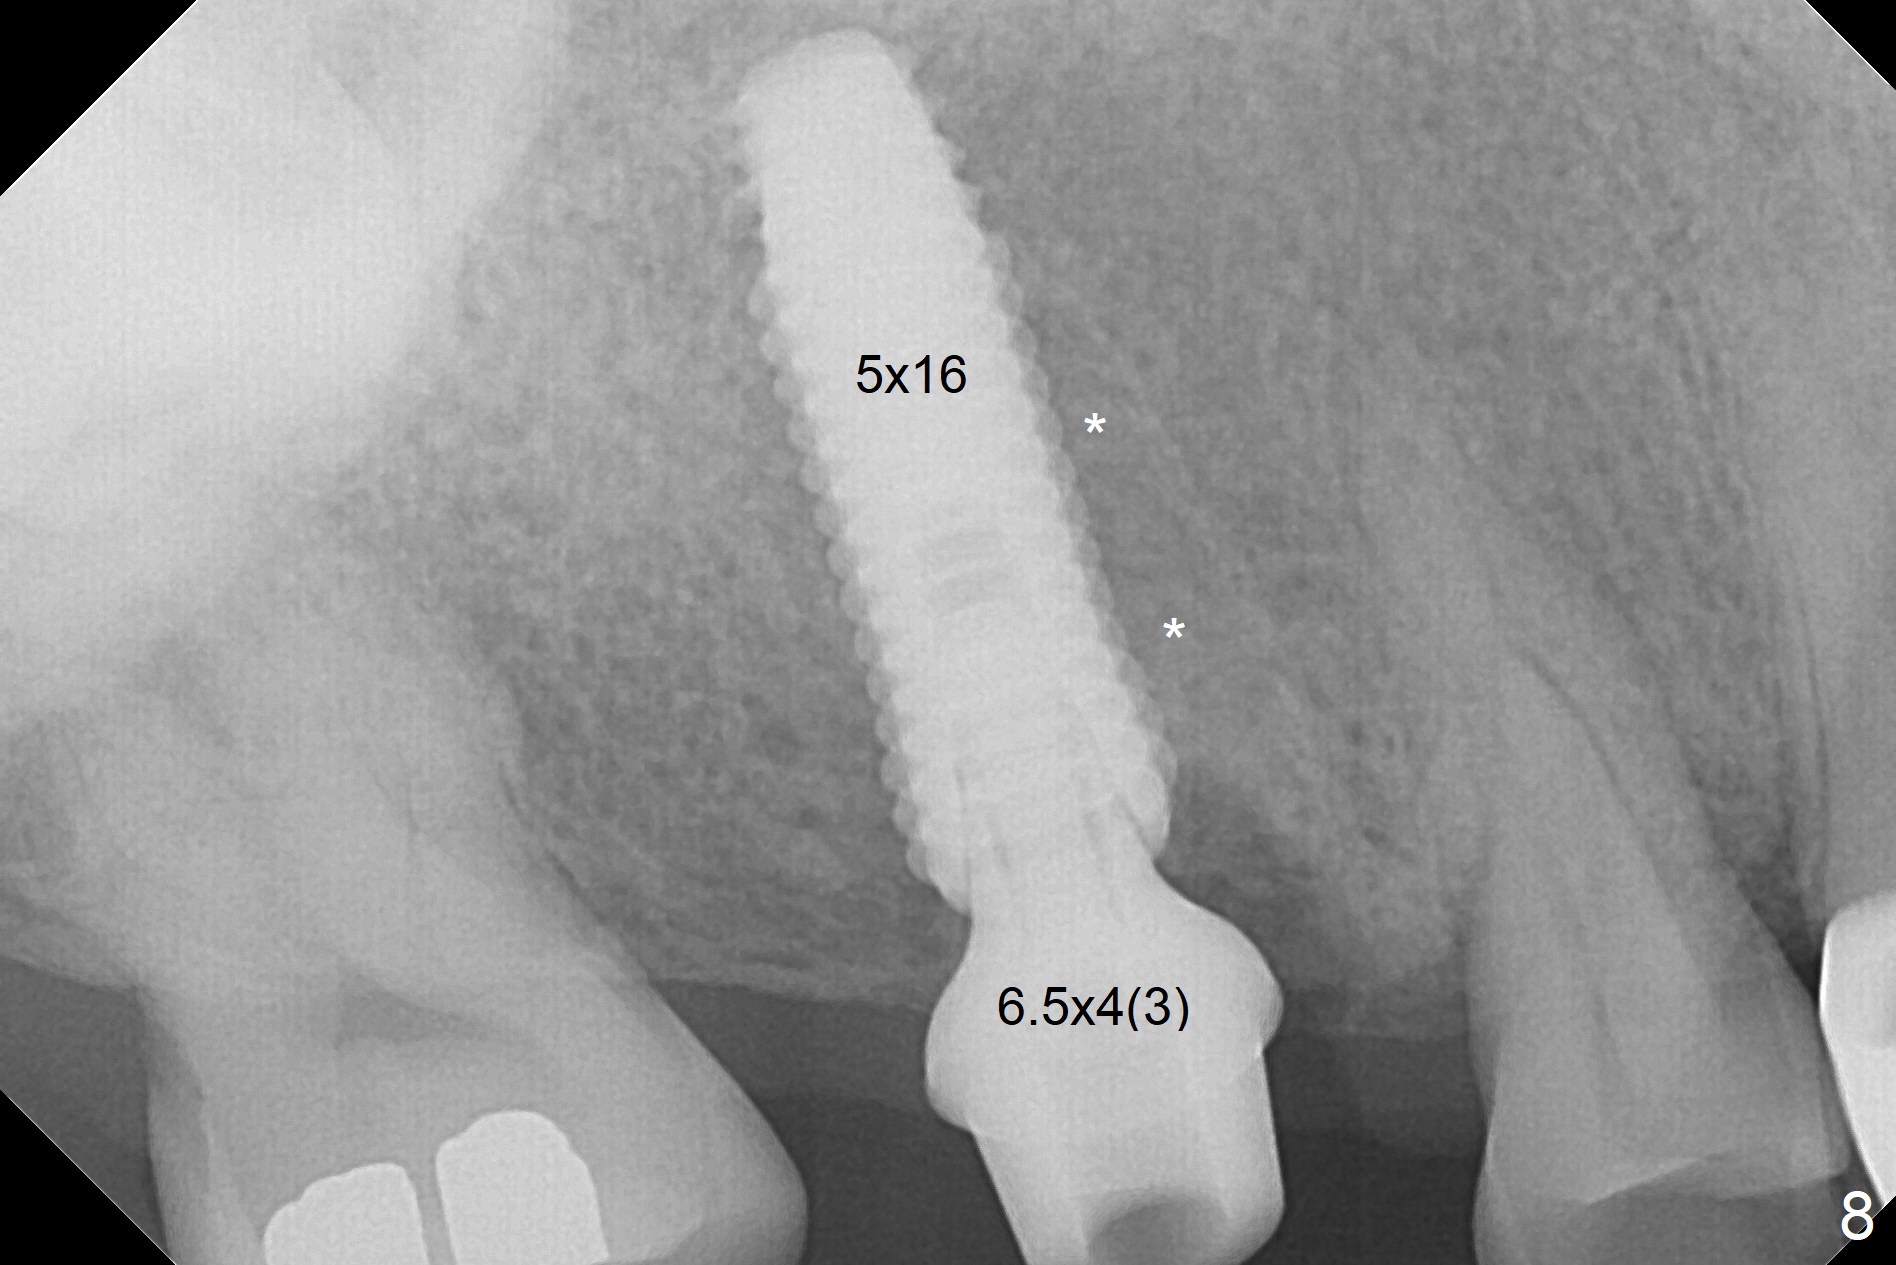

The palatal cusp of the affected 2nd premolar is apparently rotated distal (Fig.1). It is more obvious for the socket (Fig.2): the palatal (P) portion of the socket is more distal than the buccal (B) one. When the gauze is removed (Fig.3), Lindamann bur is used to remove the disto(D)palatal bone of the socket (data not shown), followed by starter drill in the DP wall obliquely (Fig.3'). Once the drill enters the bone for 1-2 mm, the bur is straightened and pushed slightly distal (Fig.3''). Fig.4 shows a parallel pin distal (overcorrect) to the original socket (Fig.4 red dashed line). Sequential osteotomy is conducted until 3.8x13 mm drill for 18 mm (Fig.5): note the 2 steps of the osteotomy (red lines). Since the apical portion of the osteotomy is larger than the drill, a larger implant than expected (5x16 mm) is placed. The implant ends up in the middle of the edentulous area (due to the stepped osteotomy; Fig.6-9; >60 Ncm). Vera allograft is placed (Fig.7-9 *) prior to and after placement of a 6.5x4(3) mm abutment (Fig.8-10). The remaining socket opening is sealed with a piece of Collagen plug (Fig.10 *). The socket is then closed by an immediate provisional (Fig.11 P). The abutment is retightened 2 months postop (Fig.12,13). The crown is cemented 4.5 months postop. Panoramic X-ray and CT are taken nearly 7 months post cementation (Fig.14,15) when the patient is ready for #30 implant guide preparation.